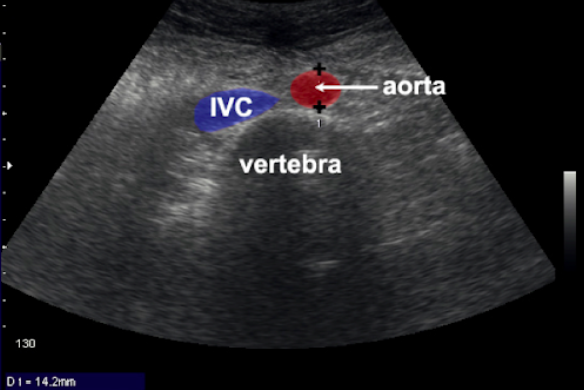

- Aneurysm: abnormal dilatation of a blood vessel more than 50% its normal diameter

- AAA: dilatation of the AA greater than 3cm, every 8mm increase there is 34% more chance of death

How do you investigate a suspected AAA (not ruptured)?

- US

AAA most commonly infrarenal